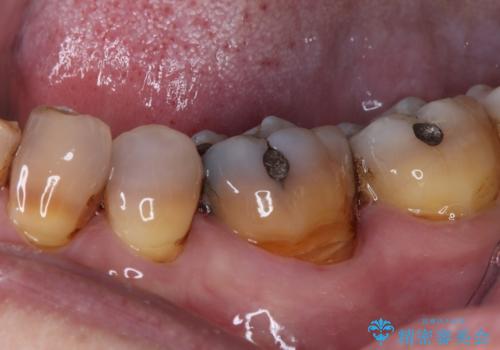

- 上顎大臼歯が食事の度に痛みを感じるとのことで来院された患者様です。

レントゲン写真などで診査を行ったところ、神経組織が壊死し、根尖部周辺の骨に炎症が認められました。